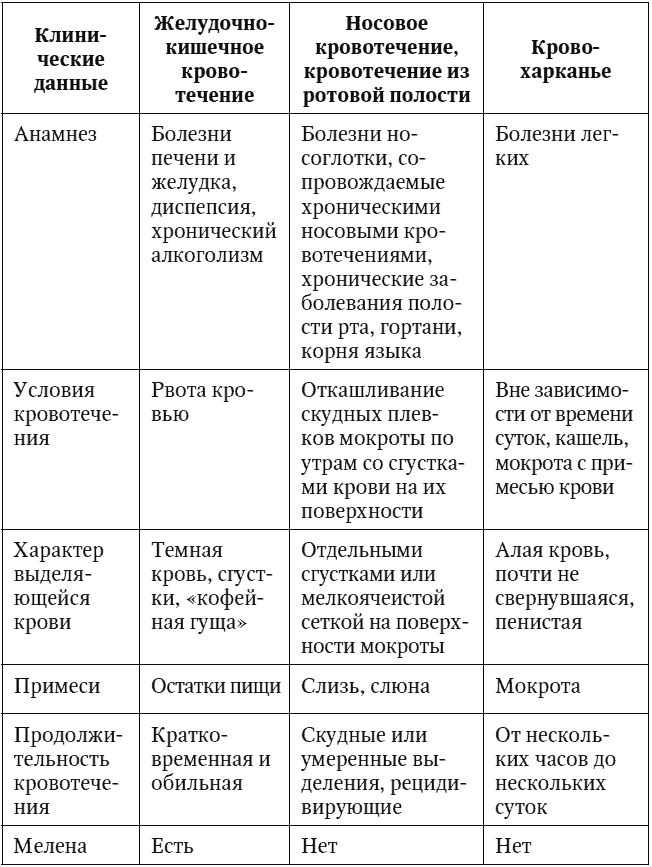

В перечисленных случаях речь идет о так называемом ложном кровохарканье. Дифференциальные отличия ложного и истинного кровохарканья представлены в табл. 2.

Таблица 2

Дифференциальная диагностика при кровохарканье

Как видно из таблицы, принципиальными факторами, требующими учета при проведении дифференциальной диагностики между ложным и истинным кровохарканьем, являются: анамнез, условия кровотечения, а также характер выделяющейся крови, наличие примесей и продолжительность кровотечения.

Так, при наличии анамнестических данных за заболевания желудочно-кишечного тракта (эрозивно-язвенные поражения, заболевания печени, в том числе на фоне хронического алкоголизма и пр.) необходимо исключение желудочно-кишечного кровотечения. Кроме того, следует учитывать, что при ЖКК наблюдается рвота с кровью, которая имеет темный цвет, приобретая вид «кофейной гущи», а также развитие мелены. Носовое кровотечение или кровотечение из полости рта можно предположить при наличии в анамнезе заболеваний полости рта, носоглотки, в том числе злокачественных новообразований. При этом происходит откашливание скудных плевков мокроты по утрам со сгустками крови на их поверхности.

В тех же ситуациях, когда в анамнезе имеются заболевания бронхолегочной системы, а также сердечно-сосудистая патология, сопровождающаяся явлениями легочной гипертензии, можно предположить наличие именно «истинного» кровохарканья. В этих случаях наблюдается отхождение мокроты с примесью крови, преимущественно не зависящее от времени суток и продолжающееся от нескольких часов до нескольких дней.